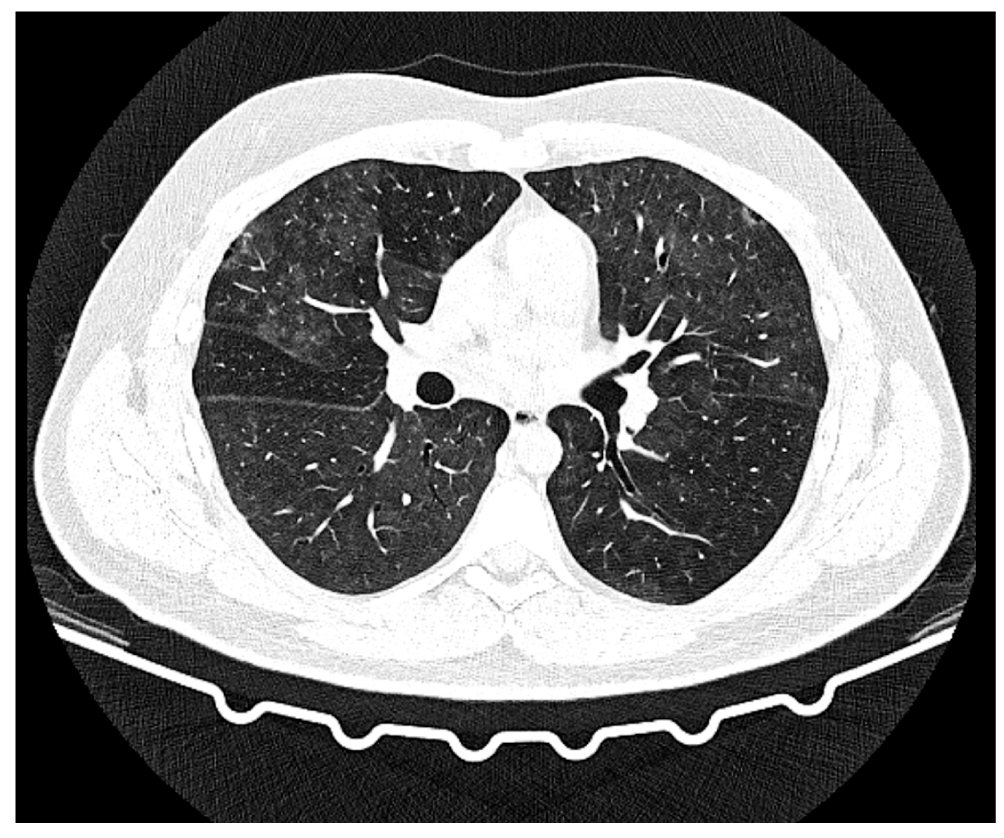

Fig. 7. Axial sections showing changes at the level of the upper parts of the lungs over time, pulmonary window: a: chest CT scan dated May 18, 2022, day 8 of the disease, day 3 of hospitalization; b: chest CT scan dated June 2, 2022, day 23 of the disease, day 17 of hospitalization.

Fig. 8. Axial sections showing changes at the level of the lower parts of the lungs over time, pulmonary window: a: chest CT scan dated May 18, 2022, day 8 of the disease, day 3 of hospitalization; b: chest CT scan dated June 2, 2022, day 23 of the disease, day 17 of hospitalization.

Description of the chest CT scan dated May 18, 2022, day 8 of the disease, day 3 of hospitalization (Fig. 7a, 8a). The lungs display negative infiltrative changes, with increasing extent and size, and new infiltration areas occurred in the lower lobe of the right lung. The lungs are fully expanded. Multiple segments of the lungs exhibit extensive confluent areas of heterogeneous infiltration of the consolidation type with a peripheral rim of ground glass are observed, with visible bronchial lumen. Focal masses with somewhat radial contours, measuring up to 3.8 × 5.1 mm and 7.9 × 6.2 mm, are observed in the upper S2 segment on the right side. The bronchial lumen is patent, and the intrathoracic or axillary lymph nodes are not enlarged. Free fluid in the pleural cavities is observed on both sides. On the right side, the fluid extends up to 7–8 mm (previously 5–6 mm), whereas on the left side, the fluid reaches up to 6 mm (previously 2–4 mm). The heart is unremarkable. Results: CT pattern of negative changes in bilateral multifocal pneumonia and bacterial disease (legionellosis?). Focal lesions in the right lung without changes and minor bilateral hydrothorax with slightly negative changes.

Description of the chest CT scan dated June 2, 2022, day 23 of the disease, day 17 of hospitalization (Fig. 7b, 8b). Compared to the previous CT scan on May 18, 2022, there is a notable improvement in the extent, size, and intensity of infiltration in the lungs. The lungs are fully expanded. Multiple segments of the lungs show rare confluent areas of heterogeneous infiltration, characterized by heavy consolidation and ground glass appearance. Focal masses with somewhat radial contours, measuring up to 3.8 × 5.1 mm and 7.9 × 6.2 mm, are observed in the upper S2 segment on the right side. The bronchial lumen is patent, and the intrathoracic or axillary lymph nodes are not enlarged. Free fluid in the pleural cavities on both sides remains undetermined (previously noted on the right up to 7–8 mm, on the left up to 6 mm). The heart is unremarkable.

Results: CT pattern of positive changes of bilateral multifocal pneumonia (stage of incomplete resolution). Focal lesions in the right lung. Follow-up is recommended. Minor bilateral hydrothorax shows positive changes.